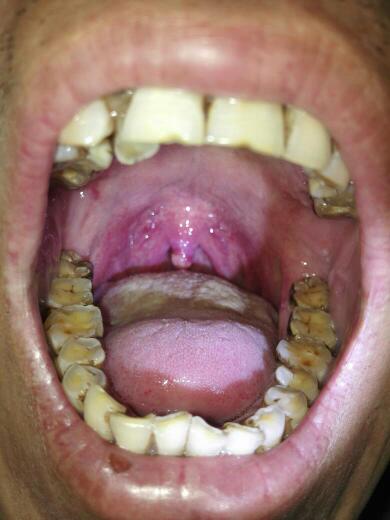

请医生看一下我的小舌头 最近感觉痰很多老是咳嗽 嗓子有异物感 听说

舌头根后面有个 类似小舌头的东西.